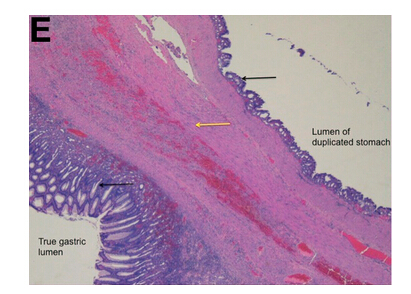

術(shù)中發(fā)現(xiàn)可疑病變具有定義不明的外科平面和顯著的周?chē)w維化,最終行空腸食管Roux-en-y吻合術(shù)。組織學(xué)檢查(圖D)和顯微鏡標(biāo)本(圖E)顯示正確診斷。

令人驚訝的是,胃大部切除標(biāo)本(圖D)檢查發(fā)現(xiàn)在疑似腫瘤的胃壁區(qū)域內(nèi)有扁平囊。這一扁平囊可以拉伸到9×8×4.5cm。胃囊與真實(shí)胃腔之間有一處共同的壁。通過(guò)此壁的組織學(xué)切片(圖E)顯示了分隔壁兩側(cè)的平滑肌細(xì)胞層和胃黏膜。這排除了GIST,證實(shí)胃重復(fù)畸形的診斷(GDC)。胃重復(fù)畸形是一種罕見(jiàn)的先天性異常,僅占胃腸道所有重復(fù)囊腫的4%至9%。大多數(shù)病例報(bào)告發(fā)生在兒童中且位于胃大彎處。GDC有以下3個(gè)特點(diǎn):(1)囊腫的壁與胃壁相連,(2)囊腫由平滑肌包圍,通過(guò)肌肉與胃壁相連,(3)囊壁排列有胃上皮或其它類(lèi)型的胃黏膜。